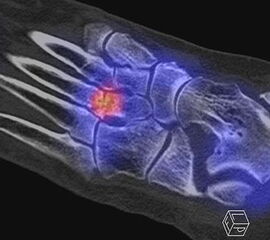

Einen solchen Fall zeigt die Abbildung 3.6., der bei uns untersucht wurde. Bei diesem Patienten bestanden chronisch persistierende Schmerzen seit 3 Jahren infolge einer Distorsion. Zwei vorhergehende MRT-Untersuchungen 1 Jahr und 2 Jahre nach dem Trauma waren nicht wegweisend. Wegen persistierender Beschwerden wurde uns der Patient zum SPECT/CT zugewiesen. Nach operativer Entfernung des Ossikels war der Patient dauerhaft beschwerdefrei.

Zum Lesen der Bildbeschreibung und zur Vollansicht bitte das Bild anklicken. Bild: H. C. Rischke

Achong beschreibt einen gleichartigen Fall mit einem mittels SPECT/CT im Sinus tarsi identifiziertes Ossikel im Sinus tarsi mit einer Größe von 8 mm 36, bei dem eine vorangehende MRT-Untersuchung gleichfalls nicht wegweisend war, weswegen eine SPECT/CT angefertigt wurde.

Auch Boulet et al. publizierten einen ähnlichen Fall 37. Sie beschreiben den Fall eines 45-jährigen Sportlers (Basketballer) mit chronischen Sprunggelenkschmerzen und lateraler Sprunggelenk-Instabilität bei Zustand nach wiederholten Sprunggelenks­distorsionen. Konservative Maßnahmen (Tape-Verbände, Physiotherapie) waren erfolglos. Es bestanden neben der lateralen Sprunggelenk-Instabilität auch ein Druckschmerz am Sinus tarsi. Im Röntgen konnte ein Ossikel im Sinus tarsi abgegrenzt werden, im MRT ein Längsriss der Peroneaus brevis Sehne, ein Ödem in dem Ossikel und im Tarsus. Im SPECT/CT zeigte sich korrespondierend ein deutlicher Hypermetabolismus in dem Ossikel. Zunächst erfolgte eine operative Stabilisierung der Sprunggelenk-Instabilität, welche jedoch keine Beschwerdefreiheit erbrachte. Erst die Resektion des Ossikels führte zur Beschwerdefreiheit.